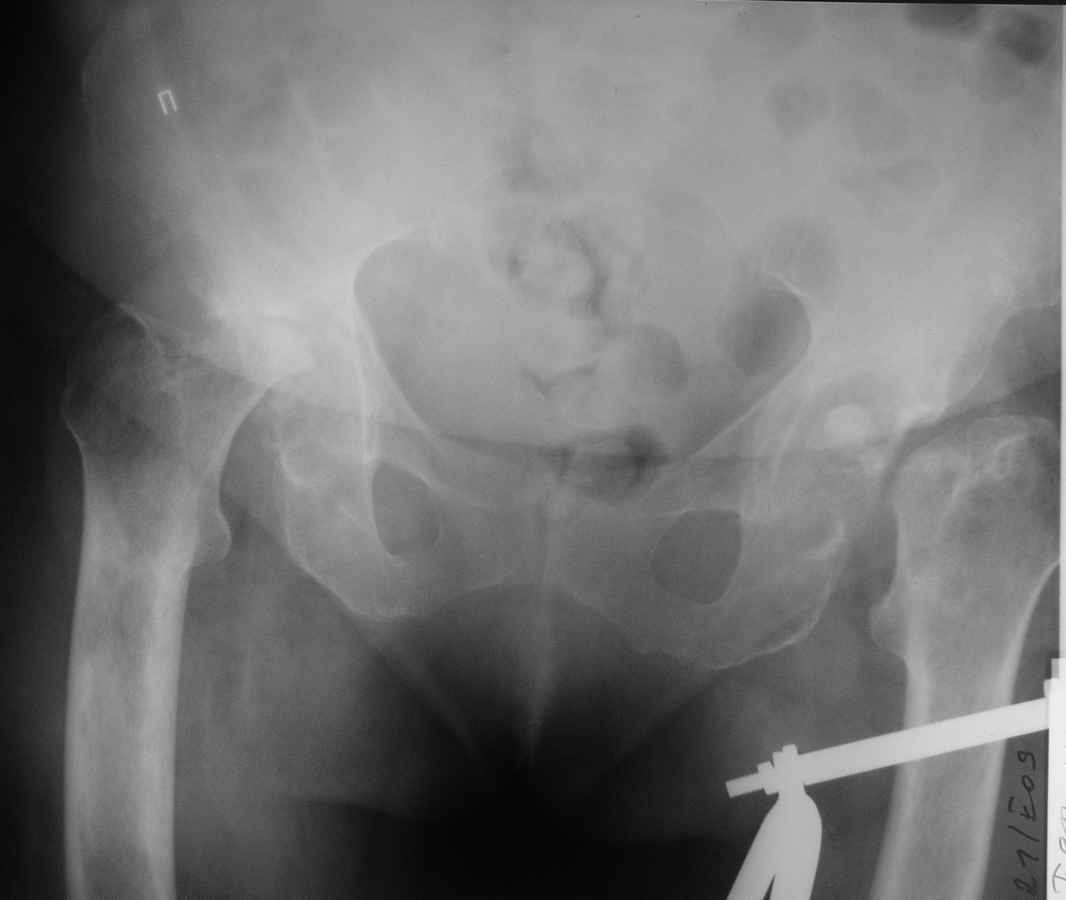

Здравствуйте уважаемые коллеги. Поступила женщина 60 лет с переломом левого бедра в н/3 диафиза, травма произошла около 2-х недель назад, упала дома.

При сборе анамнеза установлено, что в течении 3-х последних лет больную беспокоили боли в тазобедренных суставах, и уже около 1,5 лет она передвигается только на сидячей каталке. При дополнительном обследовании выявлена данная рентгенологическая картина. Факт какой-либо травмы отрицает, поражения мелких и средних суставов кистей и стоп нет, в анализе крови – СОЭ – 60мм/ч, лейкоцитоза нет. Помогите, пожалуйста, определиться с диагнозом, какие исследования необходимо провести. По тактике лечения – планируем интрамедуллярный остеосинтез левого бедра, эндопротезирование тазобедренного сустава справа. После сращения бедра – эндопротезирование левого тазобедренного сустава.